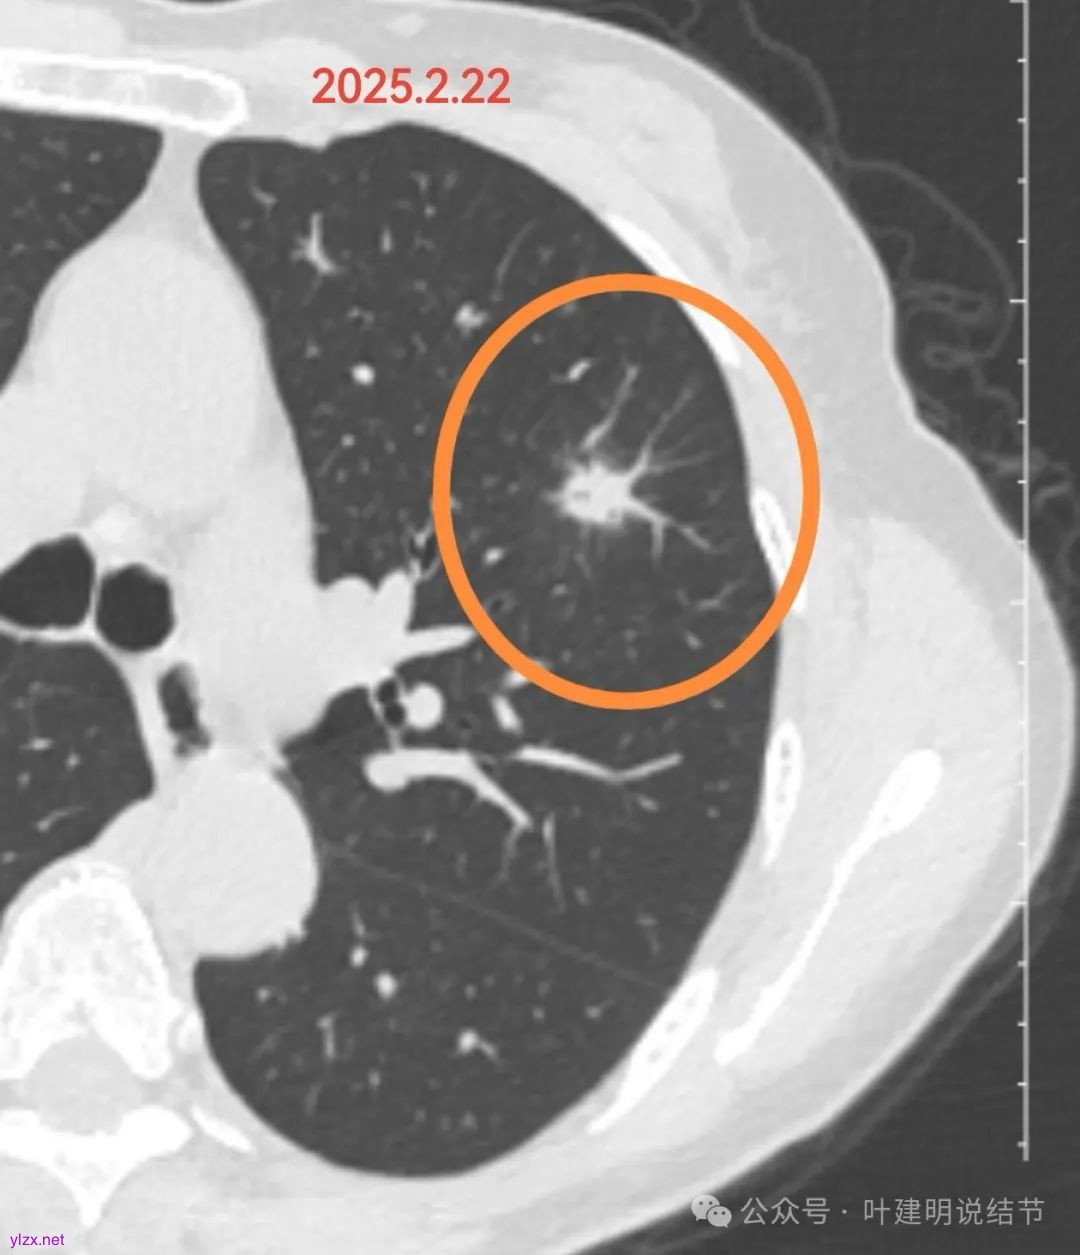

左肺上叶混合磨玻璃密度结节,大部分实性,边缘模糊,灶内不是很致密,边上有血管。关键是2024年9月同样位置没有任何异常。这个病灶首先要考虑感染性,给予口服消炎治疗并复查当然是非常合理的。